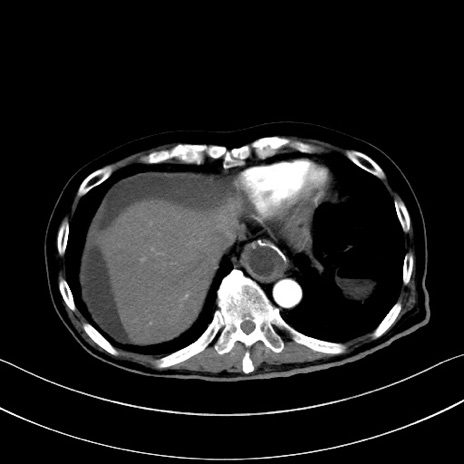

症例28(横断像)

【症例】60歳代男性

【主訴】嘔吐

【現病歴】胃癌にて胃全摘後。食思不振が悪化し、夜中に嘔吐することがある。

【既往歴】胃癌、胃全摘、脾摘、胆摘後

【データ】WBC 5900、CRP 10.56